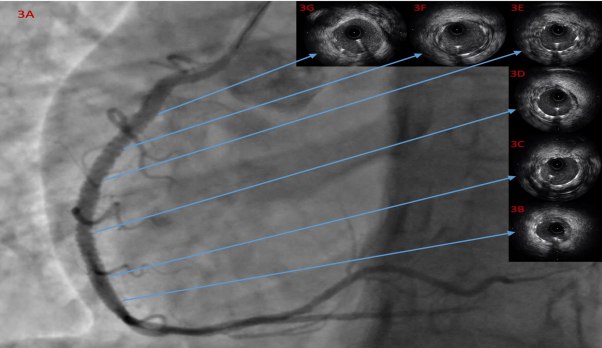

After pre-dilatation with scoring balloon, two drug eluting stents were deployed from the aforementioned and predilated 95% stenotic lesion to proximal right coronary artery and overlapping technique was performed between both stents with a non-compliant balloon. (Figure 3A). Then another IVUS assessment was run and showed excellent apposition with no edge dissection, under-expansion, marked residual stenosis or tissue protrusion. (Figures 3B, 3C, 3D, 3E, 3F and 3G).

Figure 3A. coronary angiogram RAO 30-degree view showing the angiographic result after stenting. 3B, 3C, 3D, 3E, 3F and 3G show the IVUS assessment after the percutaneous coronary intervention with excellent result.